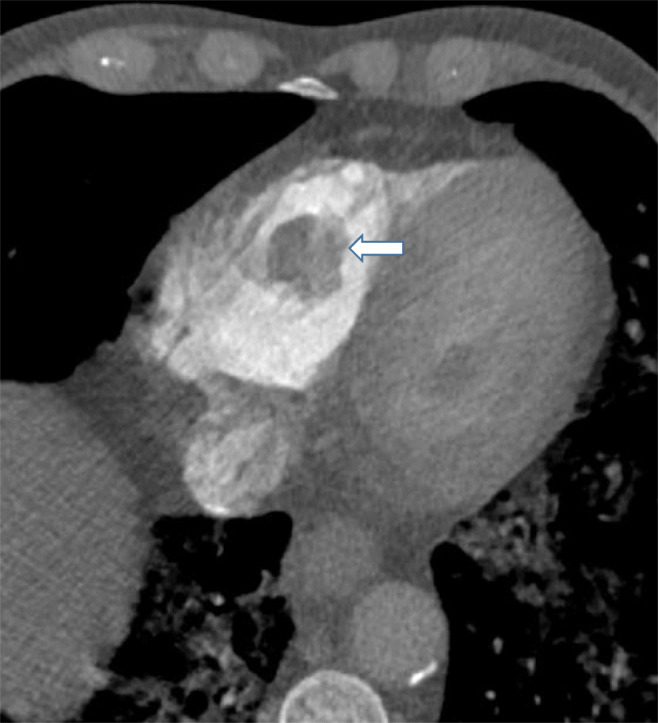

Fig. 3.

A 62-year-old man who presented with shortness of breath, cough, and fever. CTA demonstrates bilateral pulmonary ground-glass opacities, bilateral lower lobe segmental pulmonary emboli (not shown), and right ventricular thrombus (white arrow). The latter finding was confirmed on transthoracic echocardiography